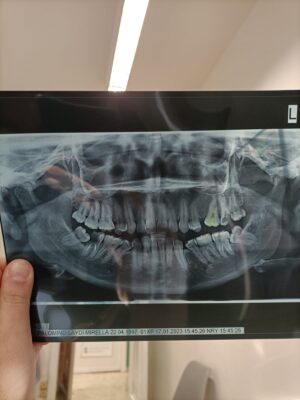

Matteo started the discussion rx planning in the forum Implant Tx Planning 2 years ago

trying to plan this case with the orthodontist.

Planning to remove all the wisdom teeth and the compromised teeth 47-27, doing ortho and after that planning to place implants in 47 and 27.